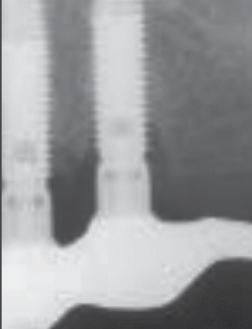

Prosthetic failure of the maxillary left premolars and first molar occurred in October 1999. The fixed partial prosthesis became loose due to recurrent decay and poor crown-to-root ratio. It was decided to extract the remaining teeth and convert to an implant-supported fixed restoration. Three Brånemark implants (Nobel Biocare, Göteborg, Sweden) were placed in the maxillary left quadrant, and the patient was referred to her dentist for the placement of a temporary removable prosthesis to restore esthetics and function while implant osseointegration was achieved. The dentist removed the maxillary right implant-supported partial prosthesis and placed an overdenture. The patient was seen in May 2000 for abutment connection on the maxillary left implants. Periapical radiographs were obtained to assess the osseointegration. Severe bone loss was observed on the implants in the maxillary right first premolar site and the maxillary right first molar site (Figs 4 to 6).

5-6

The removable prosthesis was found to be very unstable; it was rocking around the maxillary right implants and had been doing so for 6 months, according to the patient. In collaboration with the dentist, all 6 implants were splinted, and a properly fitted removable prosthesis was fabricated. Oral hygiene was reinforced to improve the patient’s home care. The peri-implant condition was re-evaluated radiographically every 3 months. The bone lesions started to heal within 3 months after elimination of the traumatic condition. At 6

months, 1.5 mm of vertical bone gain could be observed on a periapical radiograph obtained with the same angulator but without standardization (Fig 7).